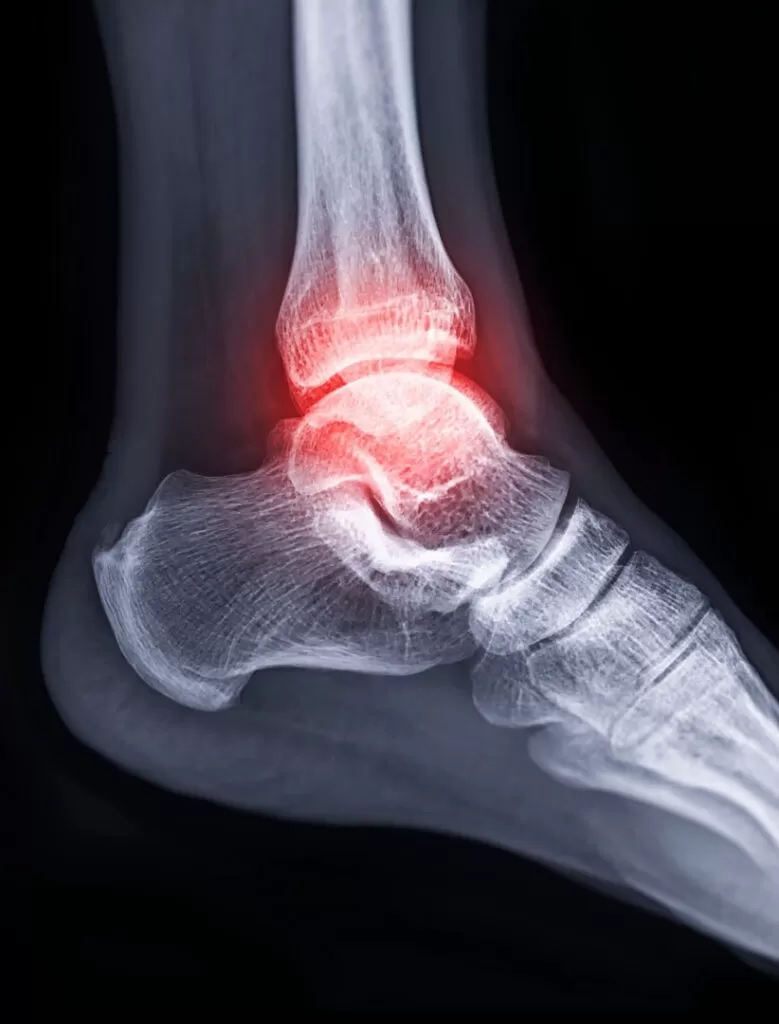

Kas ve tendonun kemiğe bağlanma yerinin inflamasyonudur. Kemik tendon bölgesinin kanlanması buradaki fibrokartilaj dokunun bariyer oluşturması nedeniyle iyi değildir. Bu nedenle bu bölgede gelişen zedelenmelerin iyileşmesi uzun sürmekte ve sıklıkla kronikleşmektedir. Kemik tendon yapışma yerinin tekrarlayan mikrotravmaları sonucu oluşur. Tekrarlayan mikrotravmalar kısmi yırtıklara ve kanamalara neden olur. Bu bölgede irritasyon ve inflamasyon oluşur. Büyüme çağındaki kişilerde tenoperiostit daha nadir görülmaktedir. Çünki bu bireylerin tendon ve kasları kemiğe oranla daha kuvvetlidir. Hatta os goog schlatter ve calcaneal apofizitte olduğu gibi inflamasyon devam eder ve kemikte fragmantasyona yol açabilir. Tenoperiostit sıklıkla, dirsek bölgesinde (tenisci dirseği, golfcü dirseği), kasıkta adduktor longusun yapışma yerinde, dizde patellar tendonun proksimal ve distal bağlantı bölgelerinde, aşil tendonunun kalkaneusa bağlanma yerinde ve plantar fasianın kalkaneusa bağlanma yerinde (plantar fassiit) oluşabilmektedir. Tendon ve kasın kemiğe yapışma yerinde ağrı, hafif şişlik, fonksiyonda bir miktar kayıp, yapışma yerine hafif bası ile hassasiyet, ilgili kas grubunun kasılması ile yapışma yerinde ağrının artması ile karekterize şikayetler mevcuttur.